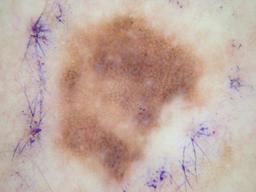

Training set from the ISIC 2016 Challenge. The "Skin Lesion Analysis Towards Melanoma Detection" challenge leverages a dataset of annotated skin lesion images from the ISIC Archive, The dataset contains a representative mix of images of both malignant and benign skin lesions.

{

"age_approx": 80,

"anatom_site_general": "upper extremity",

"clin_size_long_diam_mm": "4.00",

"concomitant_biopsy": true,

"diagnosis_1": "Benign",

"diagnosis_2": "Benign melanocytic proliferations",

"diagnosis_3": "Nevus",

"diagnosis_4": "Nevus, Atypical, Dysplastic, or Clark",

"diagnosis_confirm_type": "histopathology",

"family_hx_mm": true,

"image_type": "dermoscopic",

"melanocytic": true,

"personal_hx_mm": true,

"sex": "male"

}